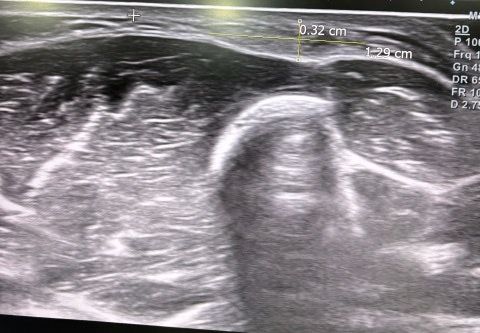

해당 사진은 병원에서 찍은 초음파이고 의사 분께서는 지방종이니 수술을 원하면 없앨 수 있다고 하셨는데 지방종이 맞을까요?

해당 종양은 3년 정도 전에 생겼고 팔에 2개 정도가 5센치 간격으로 동그란 공처럼 만져집니다

초음파만으로 확정 진단을 말하기는 조심스러우나, 제공하신 이미지와 설명을 근거로 보면 의사가 지방종(lipoma)이라고 판단한 흐름은 타당한 편입니다.

1. 초음파 소견상 지방종이 의심될 때의 특징

피하층(subcutaneous fat) 내부에

주변 지방과 유사한 밝기(저에코~등에코) 구조가 보이고

비교적 균일하게 층층이 보이는 섬유격막(striation) 이 관찰됩니다.

현재 사진에서도 피하층 내에 그런 패턴이 보여 지방종과 어느 정도 일치합니다.